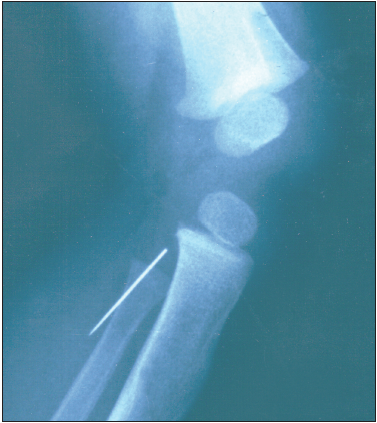

Digital duplication may be radial (preaxial or thumb), ulnar (postaxial or little finger), or central.